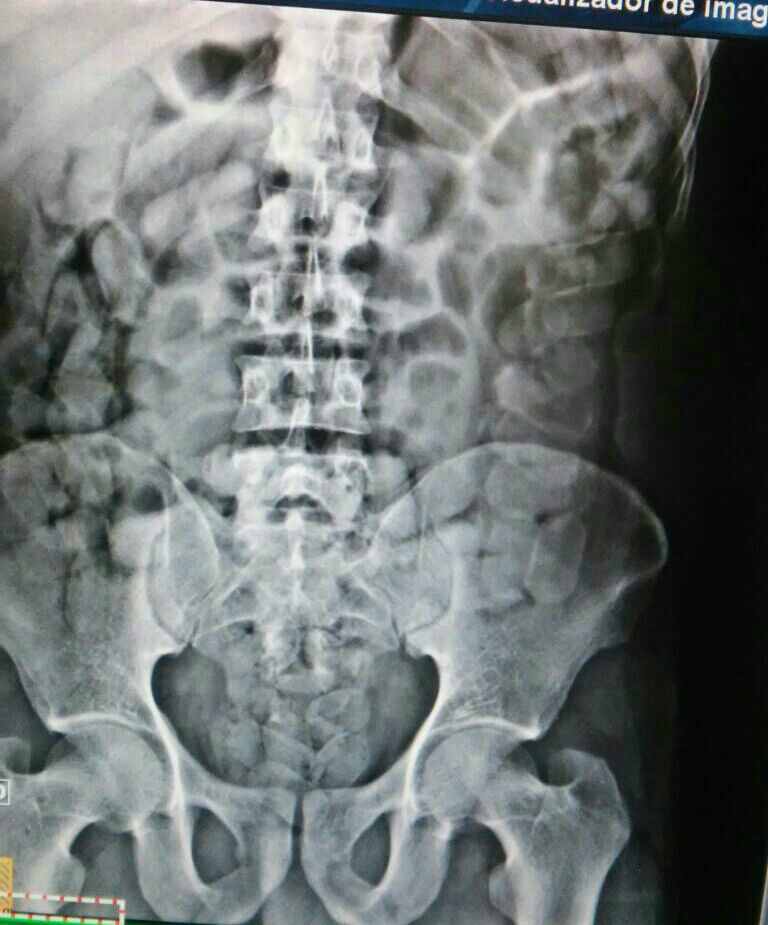

O carro foi perseguido por duas viaturas da Rotai sendo detido na rua Egídio Thomé com três homens e uma mulher, um dos homens trajando camisa laranja o qual foi alvo das denúncias e foi encaminhado ao Hospital Auxiliadora, onde após R-X foi constatado a cocaína em seu estômago.